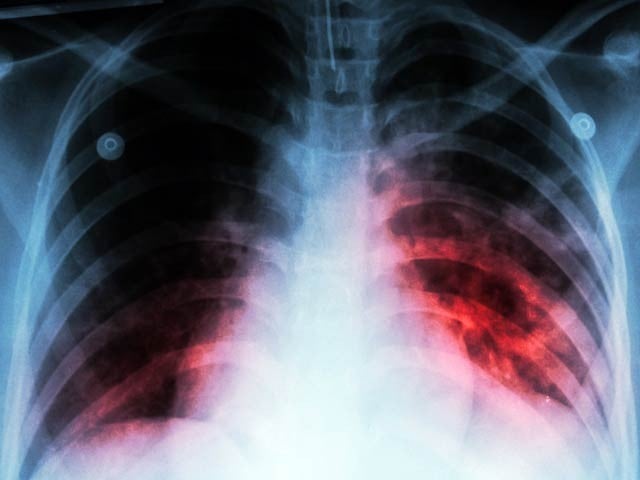

A proper and balanced diet can reduce the fatality of TB by 50%. Photo: File

Cape Town: Despite all the medical advances, TB (tuberculosis) patients are still present in the world, while it is a major medical challenge in Pakistan. Experts have presented more evidence of this.